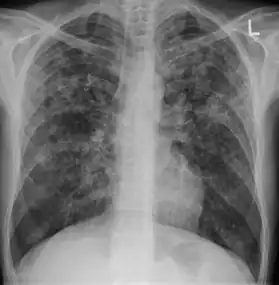

Tuberculosis creates cavities visible in x-rays like this one in the patient's right upper lobe.

A posterior-anterior (PA) chest X-ray is the standard view used; other views (lateral or lordotic) or CT scans may be necessary.

In active pulmonary TB, infiltrates or consolidations and/or cavities are often seen in the upper lungs with or without mediastinal or hilar lymphadenopathy.[1] However, lesions may appear anywhere in the lungs. In HIV and other immunosuppressed persons, any abnormality may indicate TB or the chest X-ray may even appear entirely normal.[1]